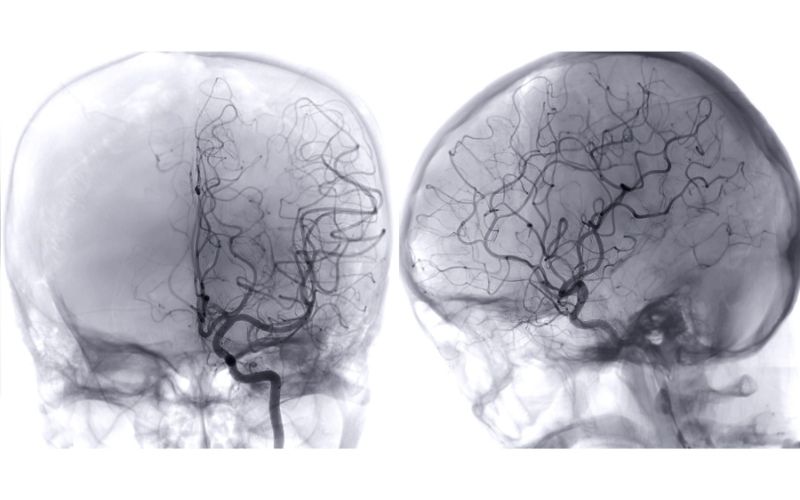

Hemifacial Spasm is a neurological disorder characterized by involuntary, repetitive twitching or contractions of the muscles on one side of the face. It is typically caused by compression of the facial nerve (cranial nerve VII) by an abnormal blood vessel near the brainstem. The continuous spasms not only affect facial appearance but can also impact speech, vision, and emotional well-being.

The first step involves a detailed neurological assessment and MRI imaging to confirm the presence of a vascular loop compressing the facial nerve. Once diagnosed, Microvascular Decompression is performed under a high-powered microscope. Through a small incision behind the ear, Dr. Gupta accesses the nerve root and carefully separates the compressing blood vessel using advanced microsurgical instruments.